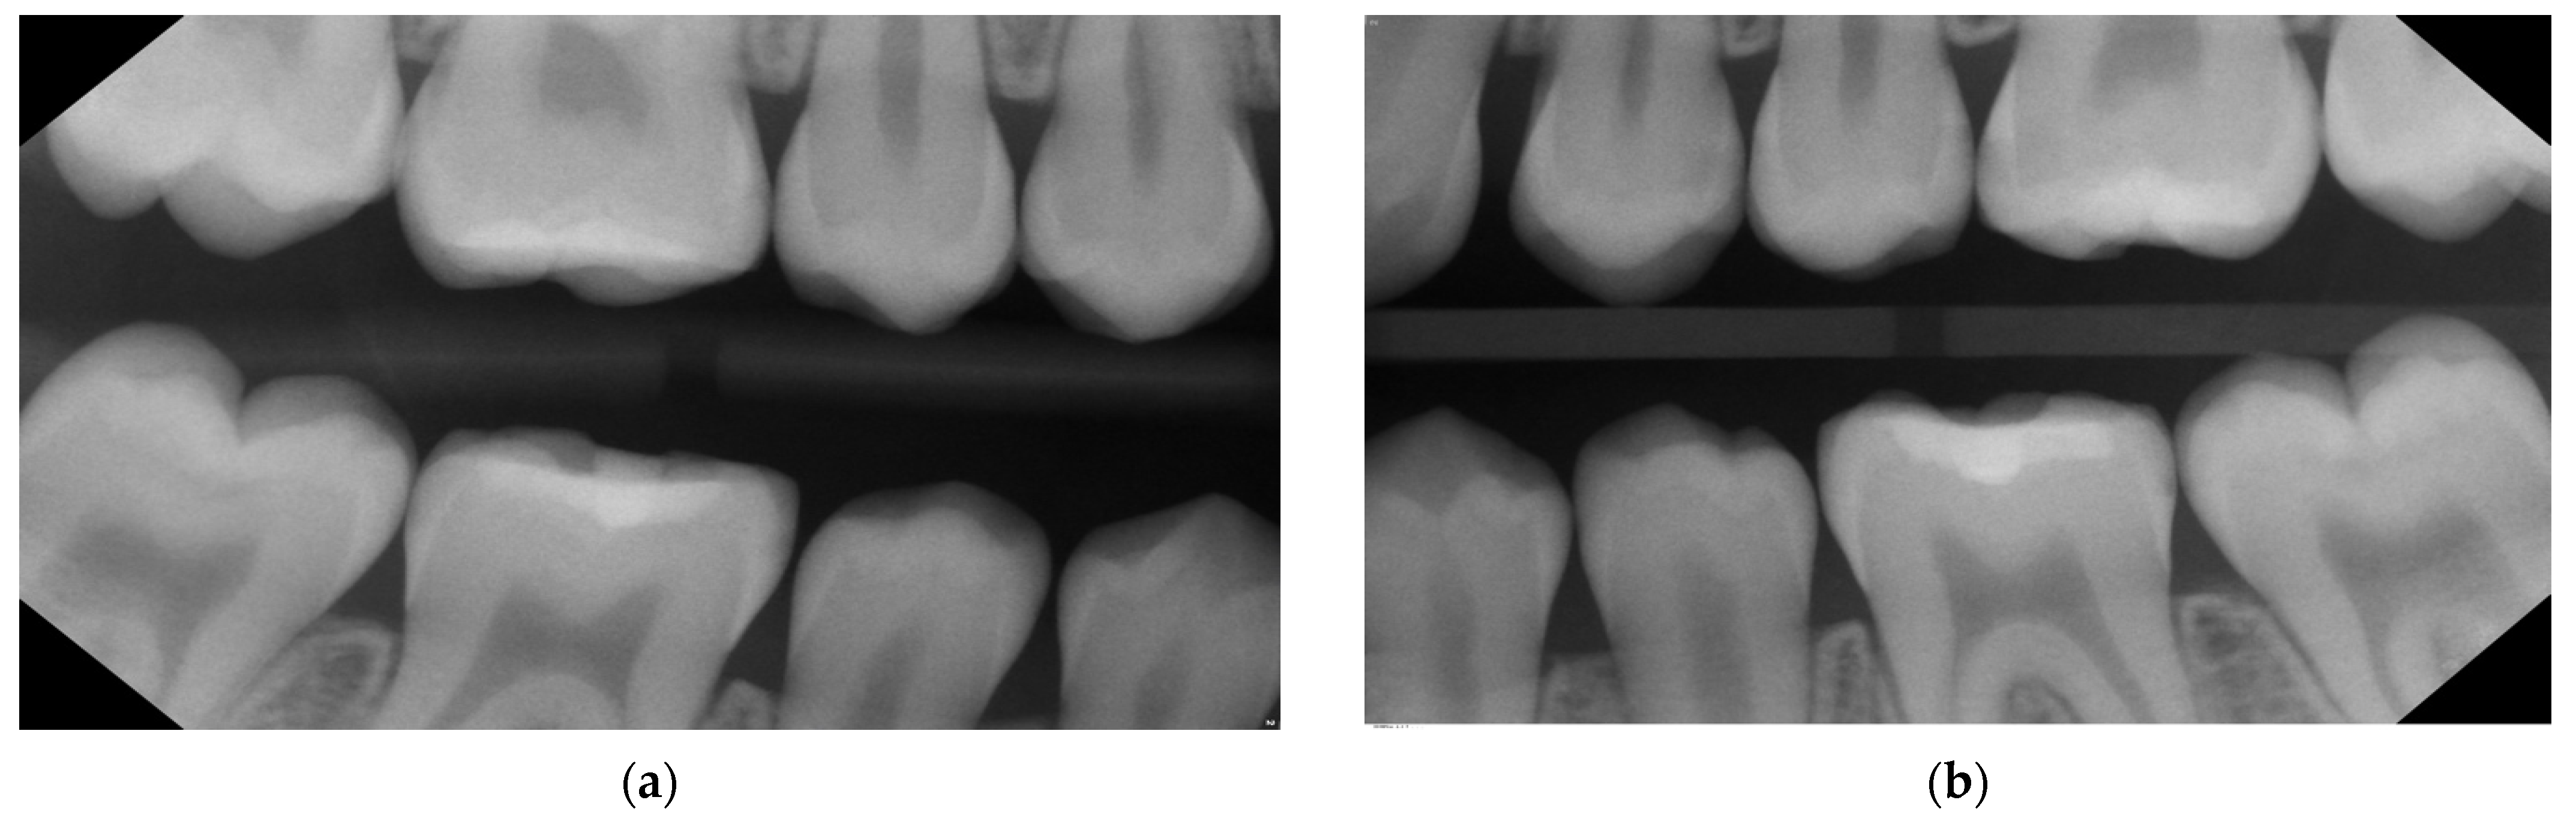

- Bitewings radiographs: During the same dental visit, bitewing X-rays were taken to confirm the presence of lesions and to determine their depth and proximity to the pulp (Figure 1). The ADA proximal caries classification system was used to diagnose and monitor progression of these lesions: E1: lesion in the outer half of the enamel; E2: lesion within the inner half of the enamel; D1: lesion passing the enamel dentin junction (EDJ) and within the outer third of dentin; D2: lesion within the 2nd third of the dentine; D3: deep lesion passing the 2nd third of the dentin [16]. For evaluations of the bitewing X-rays, three calibrated pediatric dentists classified the lesions independently in a dark room with the option to digitally modify the contrast and brightness of the X-rays. In the rare cases of disagreement, consent was reached via a discussion (Table 1). Bitewings were taken using a Sirona Heliodent DS and a Xios XG supreme intraoral sensor, with a standard dose of 0.16 mAs. The same criteria for bitewings were considered also for the follow-up visit which was at the same time the pre-SDF radiographic examination (Figure 2).

| Figure 1—11/2019 | ? | 0 | E1 | E2 | E2 | E2 | D1 | 0 | D1 | E2 | D1 | D2 | 0 | 0 |

| Figure 2—02/2022 | ? | D1 | D1 | D1 | E2 | D1 | - | - | D2 | D1 | D1 | D3 | E2 | ? |

| Figure 6—07/2023 | ? | D1 | D1 | D1 | E2 | D1 | F | 0 | F | F | D1 | F | E2 | 0 |

| Tooth | 47 | 46 | 45 | 44 | 34 | 35 | 36 | 37 | ||||||

| Surface | M | D | M | D | M | D | D | M | D | M | D | M | ||

| Figure 1—11/2019 | 0 | 0 | E1 | E1 | 0 | 0 | E2 | E1 | E2 | 0 | 0 | ? | ||

| Figure 2—02/2022 | 0 | 0 | E1 | E2 | 0 | 0 | E2 | E1 | E2 | E1 | E1 | ? | ||

| Figure 6—07/2023 | 0 | 0 | E1 | E2 | 0 | 0 | E2 | E1 | E2 | E1 | ? | 0 | ||